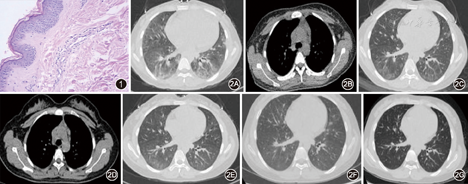

患者女,19岁,因"反复躯干、四肢皮疹伴发热1年余,加重5 d"于2017年2月18日入住广西医科大一附院呼吸内科。患者于2015年3月染发后出现头皮红斑,伴脱屑,皮疹逐渐向背部、四肢蔓延,瘙痒明显,自行涂药后皮疹无好转。同年6月出现发热,体温最高达39 ℃,无咳嗽、咳痰、气促,于7月就诊于皮肤科,查血常规:白细胞计数12.30×109个/L,中性粒细胞0.679,血红蛋白90.4 g/L,嗜酸粒细胞0.138(绝对值1.69×109个/L),血小板364×109个/L。红细胞沉降率(ESR)34 mm/1 h。血生化:丙氨酸氨基转移酶55 U/L,乳酸脱氢酶847 U/L。血红蛋白电泳检测为β-地中海贫血。肾功能、自身抗体谱、血气分析、胸部X线片结果正常。皮肤刮片真菌镜检及培养均未见异常。腹部B超示脾大。骨髓细胞形态学检查示骨髓增生近极度活跃,粒、红、巨三系增生明显活跃,嗜酸细胞增多(占8.5%)。腰部皮肤皮损病理活检示网篮状角化,表皮无萎缩变薄,基底细胞无液化变性,真皮乳头层胶原纤维蛋白增多,真皮浅层血管周围轻度淋巴细胞、少量嗜酸粒细胞浸润,累及血管壁,免疫组化IgG、IgA、IgM、C3、C1q均阴性,考虑非特异性皮炎改变(图1)。予甲泼尼龙40 mg/d静滴4 d后体温降至正常,后改为地塞米松10 mg/d静滴3 d,余予抗组胺、调节免疫治疗14 d后好转出院。出院诊断"嗜酸粒细胞增多性皮病、β型地中海贫血"。出院后予激素口服、曲安奈德益康唑乳膏外用。出院后患者反复发热伴皮疹,并逐渐出现干咳、活动后气促。同年8月31日因"皮疹、发热伴咳嗽"再次住院,查血常规:白细胞计数13.39×109个/L,中性粒细胞0.573,嗜酸粒细胞绝对值2.43×109个/L,血红蛋白108.3 g/L,血小板413.7×109个/L。FIP1L1/PDGFRα、FIP1L1/PDGFRβ融合基因均阴性。胸部CT(图2A,图2B)示:(1)两肺弥漫性渗出性病变;(2)纵隔及双侧腋窝淋巴结肿大。9月15日肺功能提示中度限制性通气功能障碍[(肺活量占预计值百分比(VC%pre)为44.5%,第1秒用力呼气量占预计值百分比(FEV1%pre)为47.6%)]、中-重度弥散功能障碍[一氧化碳弥散量(DLCO)为16.3%]。予头孢地嗪+克林霉素、泰能抗感染、甲泼尼龙抗炎,激素减量后患者发热再发,甲泼尼龙加量至80 mg/d静滴10 d后患者症状好转于9月18日出院。出院后间断发热咳嗽,同年10月返院复查,血嗜酸粒细胞结果恢复正常。10月26日查肺功能较前改善(VC%pre为65.5%、DLCO为56.4%);10月26日胸部CT(图2C)示两肺病变吸收好转。随后门诊定期复诊规则调整醋酸泼尼松用量逐渐减量至20 mg/d并维持,无新发皮疹和气促。2016年3月因服用"百令胶囊"后再次出现四肢及躯干红色皮疹、伴发热气促,自行将醋酸泼尼松加量至40 mg/d,仍有发热。查胸部CT(2016年3月15日,图2D,图2E)提示两肺间质性改变,磨玻璃影,以胸膜下为主,纵隔淋巴结增大。患者因路途遥远不规则门诊就诊,自行根据当地医院血嗜酸粒细胞结果调整醋酸泼尼松用量为20~50 mg/d,自觉皮疹、气促症状无明显改善。2016年4月第2次入住呼吸内科。血常规:白细胞计数20.73×109个/L,中性粒细胞0.808,血红蛋白103 g/L,嗜酸粒细胞0.036(绝对值0.75×109个/L)。予甲泼尼龙80 mg/d治疗2 d后体温正常,无新发皮疹,气促好转后出院,出院后醋酸泼尼松片50 mg/d治疗。2017年1月患者无明显诱因再次出现躯干、四肢红斑,脱屑伴痒觉,口服地氯雷他定干混悬剂、咪唑斯叮缓释片后皮疹好转,但症状反复并逐渐加重,自行将醋酸泼尼松片由20 mg/d调整至50 mg/d,皮疹未见明显好转,无发热,第3次住院。入院查体躯干、四肢伸侧可见散在陈旧色素沉着及多量大片红斑。双肺呼吸音粗,未闻及干湿性啰音。入院查白细胞计数16.50×109个/L,嗜酸粒细胞绝对值和百分比均正常,中性粒细胞0.883,C-反应蛋白21.12 mg/L。ESR为28 mm/1 h。血气分析、肝肾功能、超敏肌钙蛋白、血清真菌β-葡聚糖测定、自身抗体谱、降钙素原均未见异常。腹部超声未见异常。2月20日胸部CT平扫大致正常(图2F),肺功能检查提示通气功能正常、重度弥散功能障碍(VC%pre为83.9%、DLCO为28.31%)。予甲泼尼龙80 mg/d静滴治疗7 d,后减量至醋酸泼尼松片60 mg/d并加强抗组胺、护胃、补钙及对症治疗,患者全身风团消退后好转出院。出院后醋酸泼尼松片60 mg/d,激素逐渐减量至20 mg/d维持。9月6日复查胸部CT(图2G)未见异常。肺功能逐渐好转(2017年4月27日DLCO为32.10%, 9月7日DLCO为37.31%)。最终诊断为伴嗜酸粒细胞增多和系统症状的药物反应(DRESS)(累及皮肤、骨髓、肝、淋巴结、脾、肺、肌肉关节等),目前仍在随访中。

注:图1为患者腰部皮损病理学检查结果(HE ×400),具体表现为:网篮状角化,表皮无萎缩变薄,基底细胞无液化变性,真皮乳头层胶原纤维蛋白增多,真皮浅层血管周围轻度淋巴细胞、少量嗜酸粒细胞浸润,累及血管壁,个别红细胞外溢,考虑为非特异性皮炎改变。图2为患者胸部CT检查结果,具体为:2015年8月24日,两肺弥漫性渗出性病变、纵隔及双侧腋窝淋巴结肿大、心包少量积液(图2A,B);同年10月26日,两肺病变吸收好转(图2C);2016年3月15日,两肺间质性改变,磨玻璃影,以胸膜下为主,纵隔淋巴结增大(图2D,E);2017年2月20日,大致正常表现(图2F);同年9月6日,大致同前(图2G)